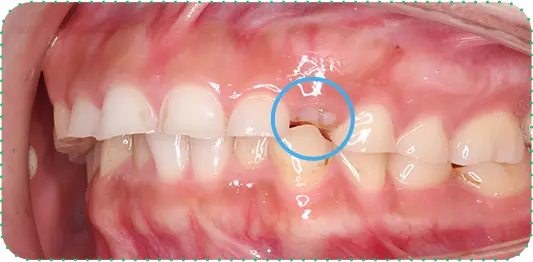

主訴

上の前歯が長くて気になる

治療期間

9か月

治療費

30万円

治療内容

右上1番を小矯正治療にて歯茎を増やし、右上1番と左上1番をセラミッククラウンにて修復

治療のリスク

咬み合わせによっては、セラミックが欠ける可能性があります。